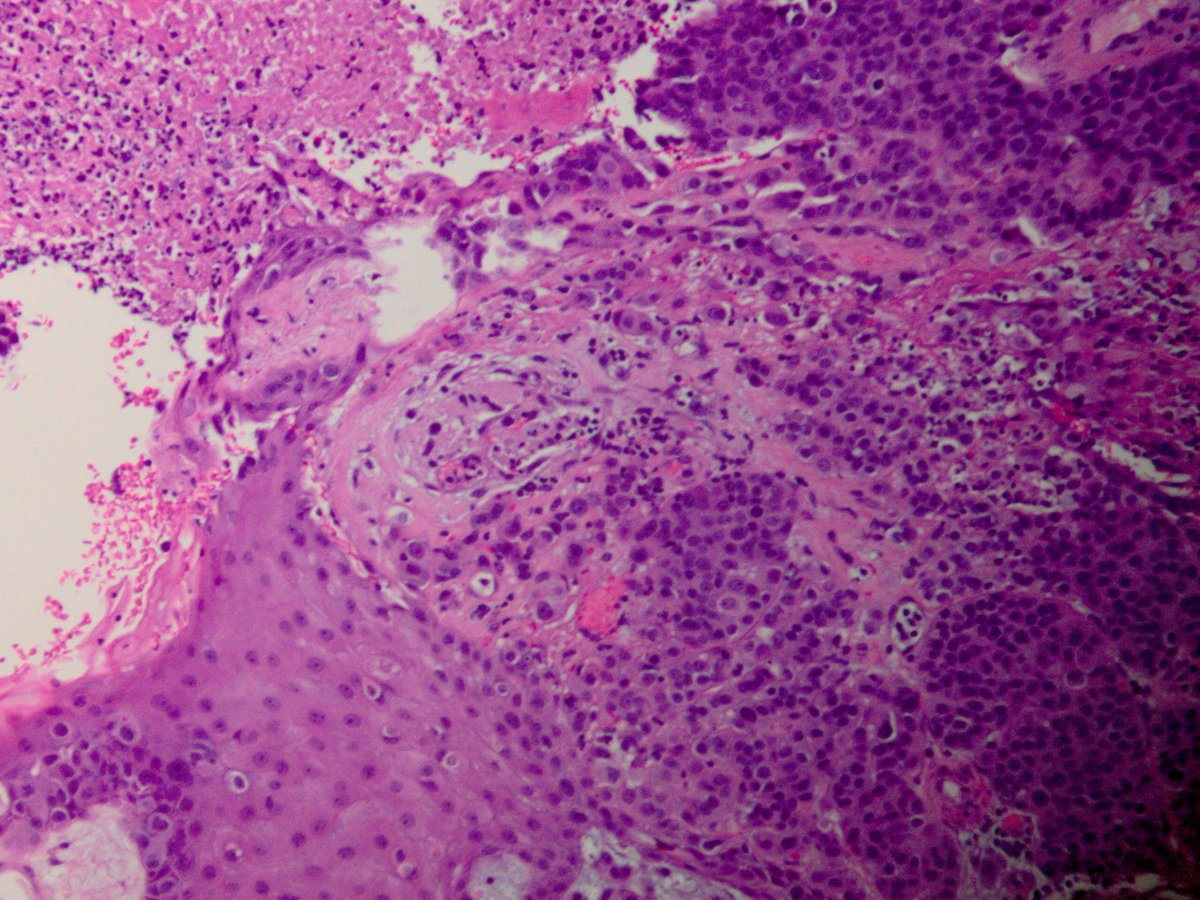

Stuart Schnitt Laura Collins Edi Brogi Jenny Pincus, MD Rola Ali, MD Raghavendra Pillappa Lorand Kis ISBP Bin Xu Xiaoyin "Sara" Jiang, MD (She/Her) Young 27 year old already with T4 breast Ca involving dermal lymphatics and causing superficial ulceration. A good example of inflammatory carcinoma of breast